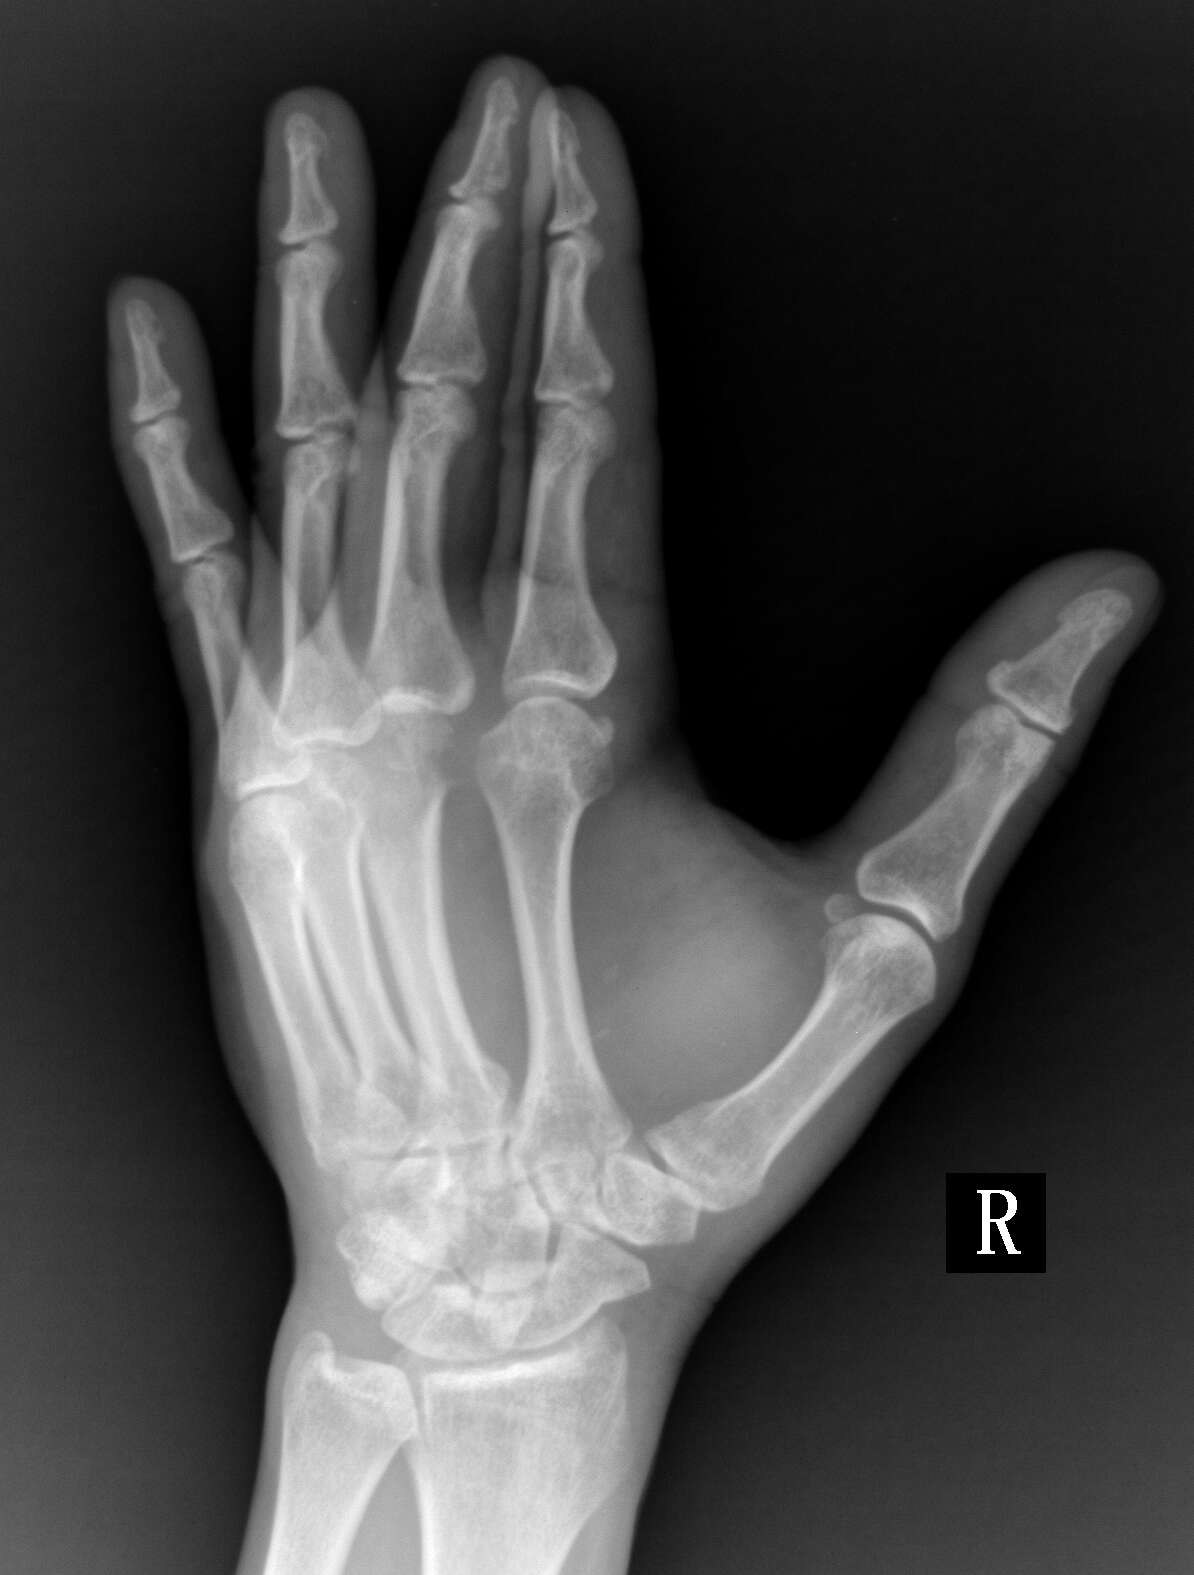

患者,男,47,右手背肿痛50天,皮肤有红肿,来拍片发现第三掌骨远端有骨质破坏,

化脓性关节炎可能性大

结合临床考虑第三掌指关节化脓性关节炎。

只有一个手指,结合临床症状,支持化脓性关节炎

考虑第三掌指关节化脓性关节炎。

单发骨边缘性骨质破坏,考虑骨结核可能性大。